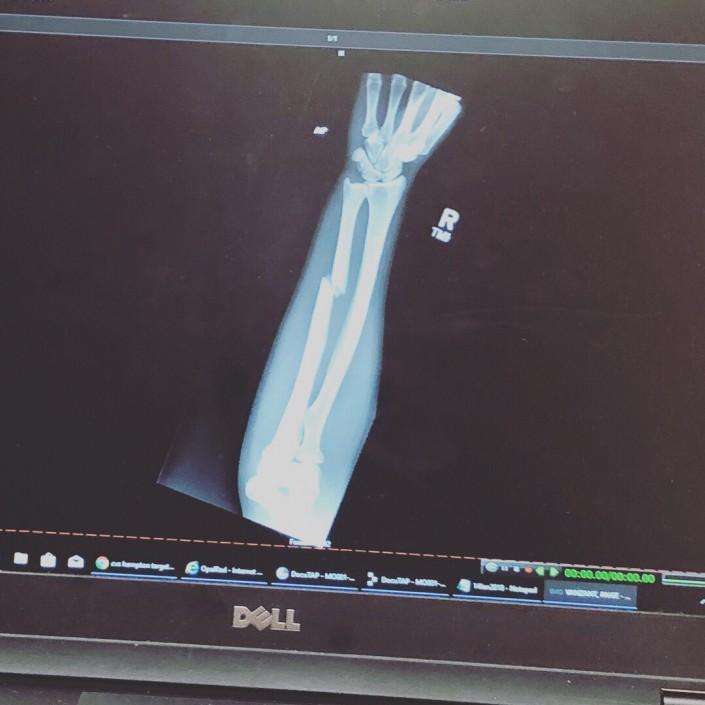

Американский боец смешанных единоборств Пейдж Ванзант сломала руку в поединке с австралийкой Джессикой-Роуз Кларк на турнире UFC в Сент-Луисе, пишет The Sun.

Травму спортсменка получила уже в первом раунде. 23-летняя американка ударила правой рукой с разворота в лоб своей сопернице. Послышался характерный звук - у Пейдж треснула кость. Однако боец выдержала все положенные три раунда, по итогам которых проиграла по очкам.

Позже пострадавшая участница соревнований опубликовала в соцсетях фотографию из больницы и рентгеновский снимок сломанной конечности.